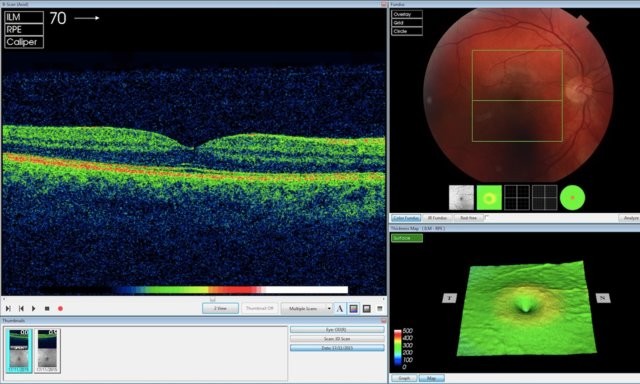

Nói cách khác, AI của DeepMind không giống như một chiếc hộp đen bí mật giúp nhả ra các kết quả. Thiết bị của DeepMind gắn các điểm ảnh lên hình ảnh quét OCT (chụp cắt lớp quang học) mắt để ánh xạ mô mắt và hiển thị các dấu hiệu bệnh cụ thể, từ đó có thể tính toán độ chính xác của những phát hiện và đề xuất của thiết bị trên cơ sở tính số %, ông Suleyman giải thích. “Điều này có ý nghĩa rất lớn”, ông nói thêm.

AI của DeepMind đang phân tích hình ảnh quét OCT (Ảnh DeepMind).